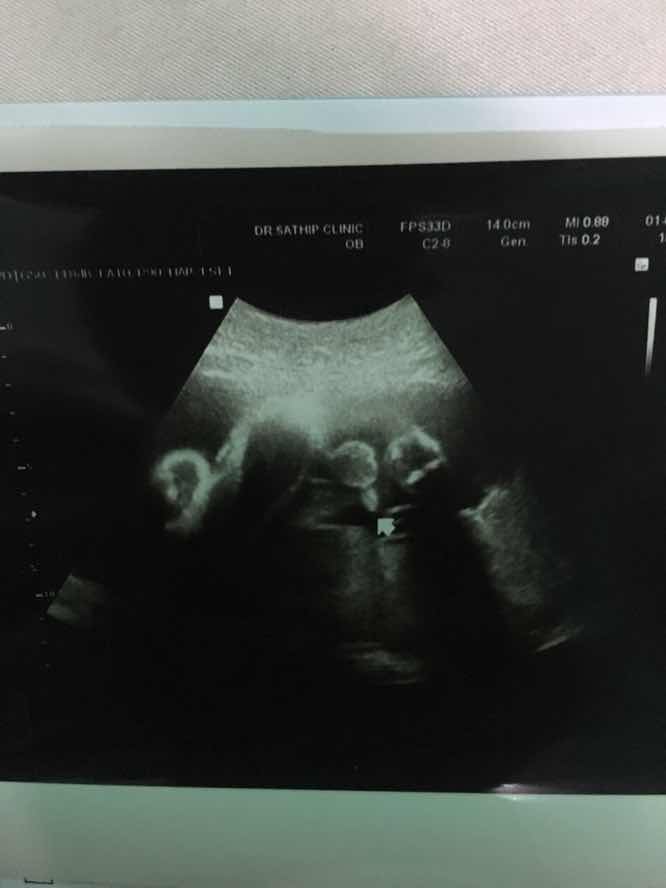

ในภาพเป็น ผช ใช่ไหมค่ะ พอดีหมอขอชัวร์ๆ เดือนหน้า เลยสอบถามแม่ๆ ที่มีประสบการณ์ลูกชาย หน่อยค่ะ ?ขอดูใบอัตตลาซาวเด็ก ผช . หน่อยจร้าาา? ถาพไม่ชัดเพราะถ่าย VDO มาจร้า ??